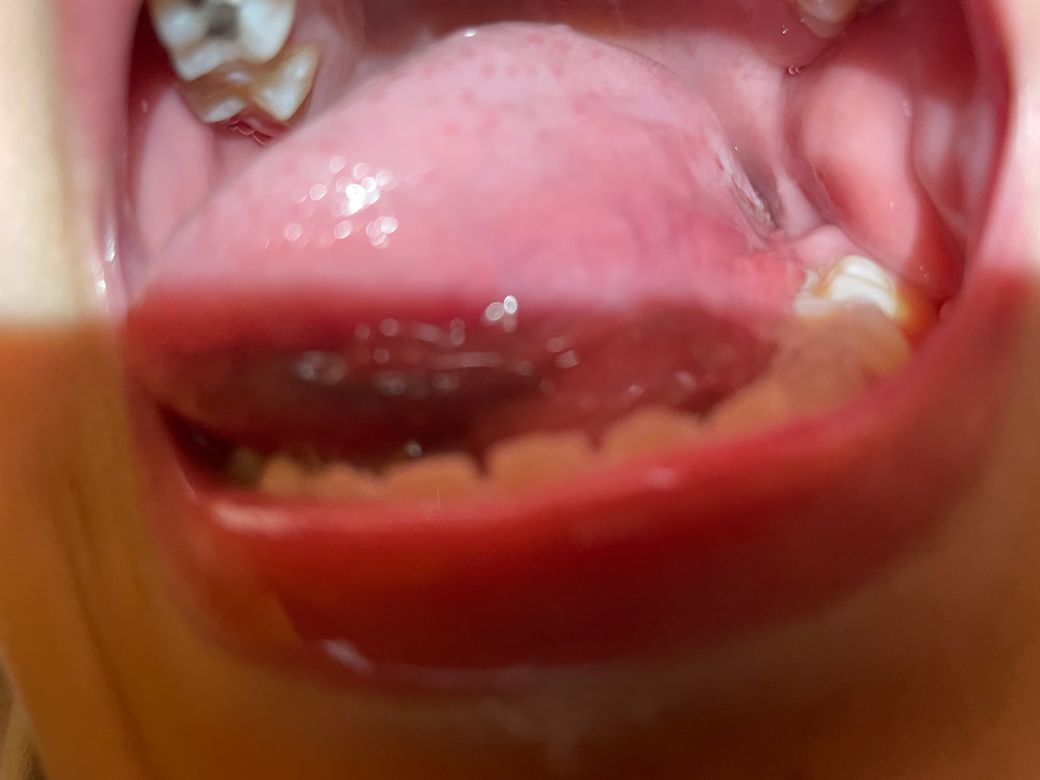

사진과 같이 11세 아들 혀 왼쪽 안쪽에 깊게 패여 낫지를 않아요..

점막의 손상은 일반적으로 특별한 치료를 하지 않더라도 수 일 내로 회복되는 것이 일반적입니다. 하지만 사진의 소견을 통해 보았을 때에는 혀 부위의 열상 같아 보이는 상처가 아물지 않은 상태인 것으로 보이며 많이 벌어져 있기 때문에 필요하다면 봉합 등 치료를 받아보는 것이 좋겠습니다. 그냥 방치하기 보다는 이비인후과에서 진료 및 치료를 받으시길 권고드립니다.